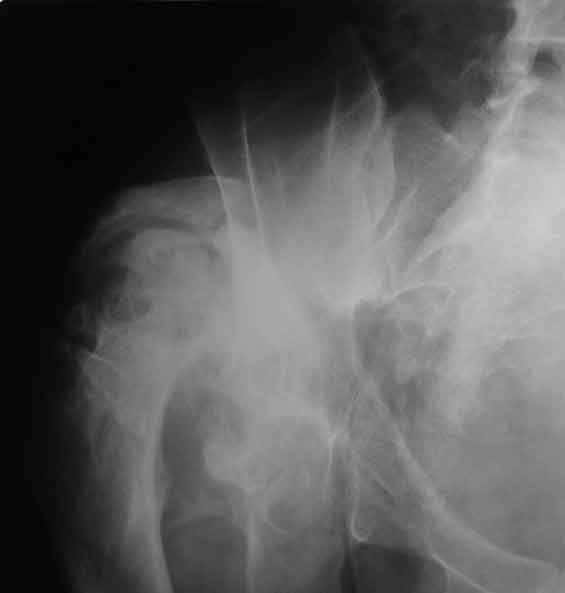

Уважаемые коллеги, пациент 30 лет, 4 года назад попал под поезд, ампутация обеих голеней в в/3, подвздошный вывих бедра (теперь застарелый). несмотря на такую ситуацию, пациент вполне прилично ходит и объем движений в неоартрозе близок к неповрежденной стороне. Основная жалоба - боль при нагрузке и в покое. Планируем двухэтапное лечение: резекция шейки, мобилизация проксимального отдела бедра, низведение бедра АВФ, вторым этапом б/ц эндопротезирование. Как поступить с головкой, вроде бы при протезировании можно будет обойтись без пластики, или ошибаюсь? Оставить ее там, где она есть? Другие варианты лечения.